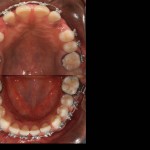

Foto e documentazione